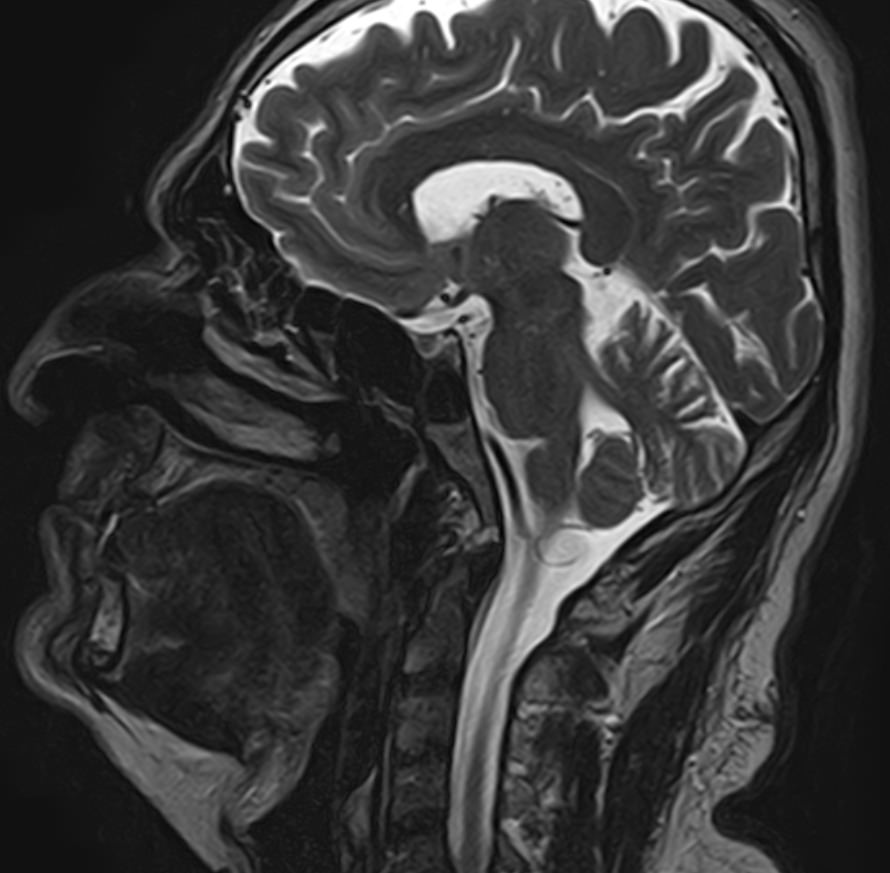

Придаточные пазухи носа представляют собой воздухоносные полости, которые располагаются в костях лицевого и мозгового черепа, выстланы изнутри слизистой оболочкой и сообщаются с полостью носа. МРТ является неинвазивным безопасным информативным способом визуализации данных анатомических областей. Метод позволяет диагностировать различные патологические процессы в области придаточных пазух носа.

Реализацию МРТ пазух носа предписывают, когда другие способы обследования больного не дают полную диагностическую картину. Это необходимо, когда нужны данные о состоянии сложно доступных клиновидных или решетчатых пазух, расположенных за костно-хрящевыми структурами черепа.

Снимки, полученные в ходе магнитно-резонансной томографии, дают подробные данные о:

• патологиях формирования пазух и полости носа;

• аномалиях строения костно-хрящевых структур;

• травмах лицевой части черепа — переломах, смещениях костных фрагментов;

• утолщениях костных стенок и слизистых оболочек;

• кистозных и опухолевых образованиях;

• злокачественных новообразованиях даже на самых начальных стадиях;

• степени симметричности околоносовых полостей;

• скоплении крови или иных жидкостей в придаточных пазухах носа.